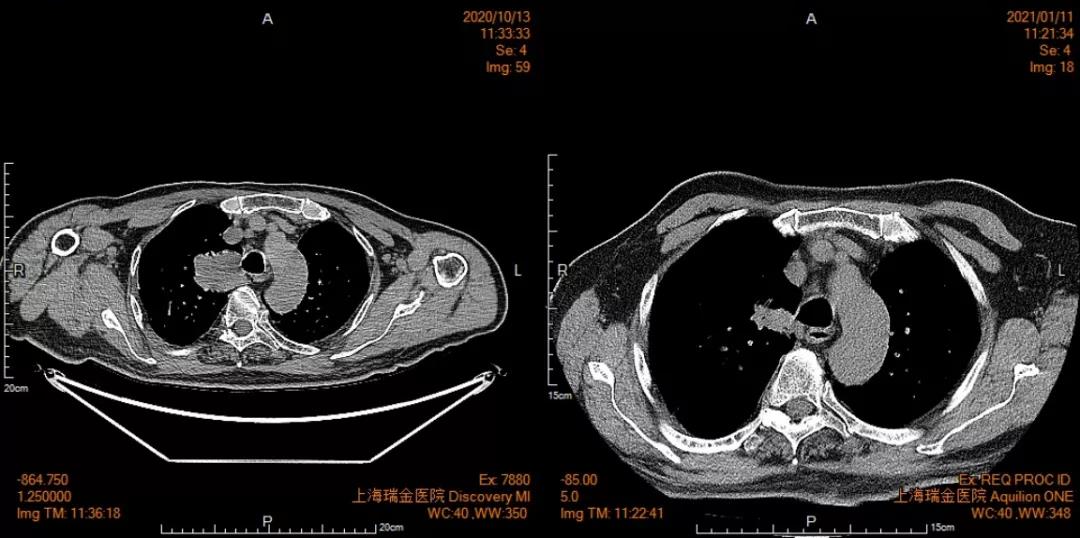

福建省肿瘤医院始终扮演着我省抗癌工作的坚强堡垒角色,并为肿瘤病人提供综合治疗,兜底全省的疑难重症癌症病人诊治工作。近年,医院强化技术创新,建立了各种肿瘤多学科诊疗的技术体系和全疾病周期的健康管理,针对每个病人的不同病情制定个体化诊疗策略,有机地在病人的不同治疗阶段合理使用,最大程度提高远期疗效,同时保障病人的生活质量,延长晚期病人生存期,使更多不可治的肿瘤得到可治。初步统计,2022年相关数据显示,在外院抗肿瘤治疗后转诊至该院进一步治疗的疑难病人治愈及好转率达 45.85%,有效率 96.5%。 当前,全院上下正坚持用党的创新理论武装头脑、指导实践、推动工作,坚持学理论、悟思想,边学习边思考,边检视边整改,切实推动党建和业务工作双融双促,努力在以学铸魂、以学增智、以学正风、以学促干上取得实效。 近期,海都记者走访了省肿瘤医院,通过一个个生动的事例,展现该院是如何让“不可治”的肿瘤变得“可治”。 五十多岁的李先生是一名EGFR突变晚期肺癌患者,经化疗、免疫治疗后,病灶仍增大,且肿瘤对三代EGFR-TKIs产生耐药。一时间乌云笼罩,治疗陷入僵局。 福建省肿瘤医院胸部肿瘤内科何志勇主任团队,针对李先生的情况仔细研究、探讨后,制定了提高三代EGFR-TKI的给药浓度的方案,最终取得令人欣喜的结果,肿瘤明显退缩。目前,李先生仍在维持治疗中,病情稳定,生活质量良好。 据悉,几乎每个EGFR突变晚期肺癌患者都要面临耐药的问题,这类患者的治疗也是目前临床上的难点和热点。福建省肿瘤医院胸部肿瘤内科何志勇主任团队一直在探索研究。 时间拉回到三年前。2019年12月,五十多岁的莆田患者李先生来到福建省肿瘤医院胸部肿瘤内科何志勇主任门诊,他患有EGFR突变晚期肺癌,且往已经接受过多种方案治疗,包括化疗、一代EGFR-TKI治疗24个月、三代EGFR-TKI治疗18个月。 “当时,患者肺部病灶增大,提示肿瘤对三代EGFR-TKI耐药,因仅肺部肿瘤增大,我们建议继续三代EGFR-TKI联合抗血管靶向治疗,患者仍有获益,无进展生存时间9个月。” 何志勇主任介绍说,后来,李先生仍由于肺部病灶的进展接受过多程的化疗联合免疫治疗,期间肺部肿瘤进展缓慢,直至2022年9月,肿瘤又出现快速进展,表现为双肺转移灶增大增多、并新增多发肝转移。 双肺转移灶增大增多,并新增多发肝转移男子接受了多方案治疗肺癌仍在增大并转移

何医生介绍,三代EGFR-TKI伏美替尼由于化学结构上的优化,具备提高药物浓度而不增加副反应的可能,国内外有相似的研究报道。因此,建议李先生开始口服“双倍剂量伏美替尼”靶向治疗。令人欣喜的是,1个月后复查,李先生肺部及肝脏转移灶较前明显退缩,疗效评价达到部分缓解。

双肺粟粒样转移和肝脏转移明显缩小

目前,李先生仍在口服“双倍剂量伏美替尼”治疗,肿瘤控制良好,已经维持稳定近一年,且并未有副作用,目前患者生活质量良好。